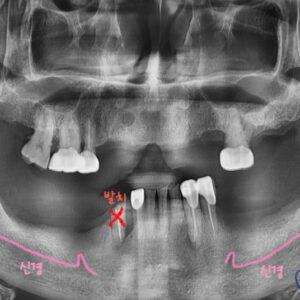

먼저 치아와 주변 뼈(치조골)의 상태를 자세히 확인하기 위해 파노라마 촬영을 시행했습니다.

파노라마 사진을 확인해 보니 위에는 치아가 상실되어 있고

아래는 치아를 잘 잡아주는 잇몸뼈(치조골)가 소실되어 흔들리고 있는 상태였습니다.

아래는 뼈이식을 하면 되고,

위에는 <상악동 거상술> 이라는 수술이 추가로 필요합니다.

통증을 유발했던 치아를 모두 발치하고 염증도 깨끗하게 제거합니다.